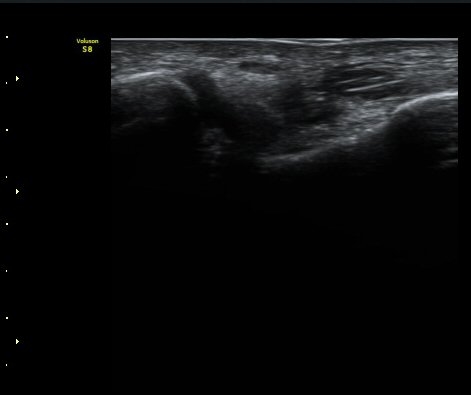

Àü°Å°ñºñ°ñÀδë Á¾´Ü¸é°Ë»ç»ó Àδë ÀδëÀÇ Àú¿¡ÄÚ ºÎÁ¾°ú(±×¸² 3)

ºñ°ñºÎÂøºÎ ¿¬°á¼º ¼Ò½ÇÀÌ °üÂûµÈ´Ù(±×¸² 4).

±×¸²3) Àü°Å°ñºñ°ñÀδë Á¾´Ü¸é°Ë»ç

±×¸²4) Àü°Å°ñºñ°ñÀδë Á¾´Ü¸é°Ë»ç